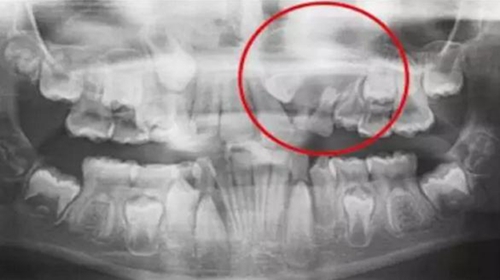

一名 23 區(qū)的9歲患者,在診所接受檢查時發(fā)現(xiàn)口內(nèi)中存在大范圍含牙囊腫[圖1]。由于上頜竇下沿出現(xiàn)大范圍突出,迫切需要接受囊腫去除手術(shù)[圖2和3]。

囊腫去除[圖2]